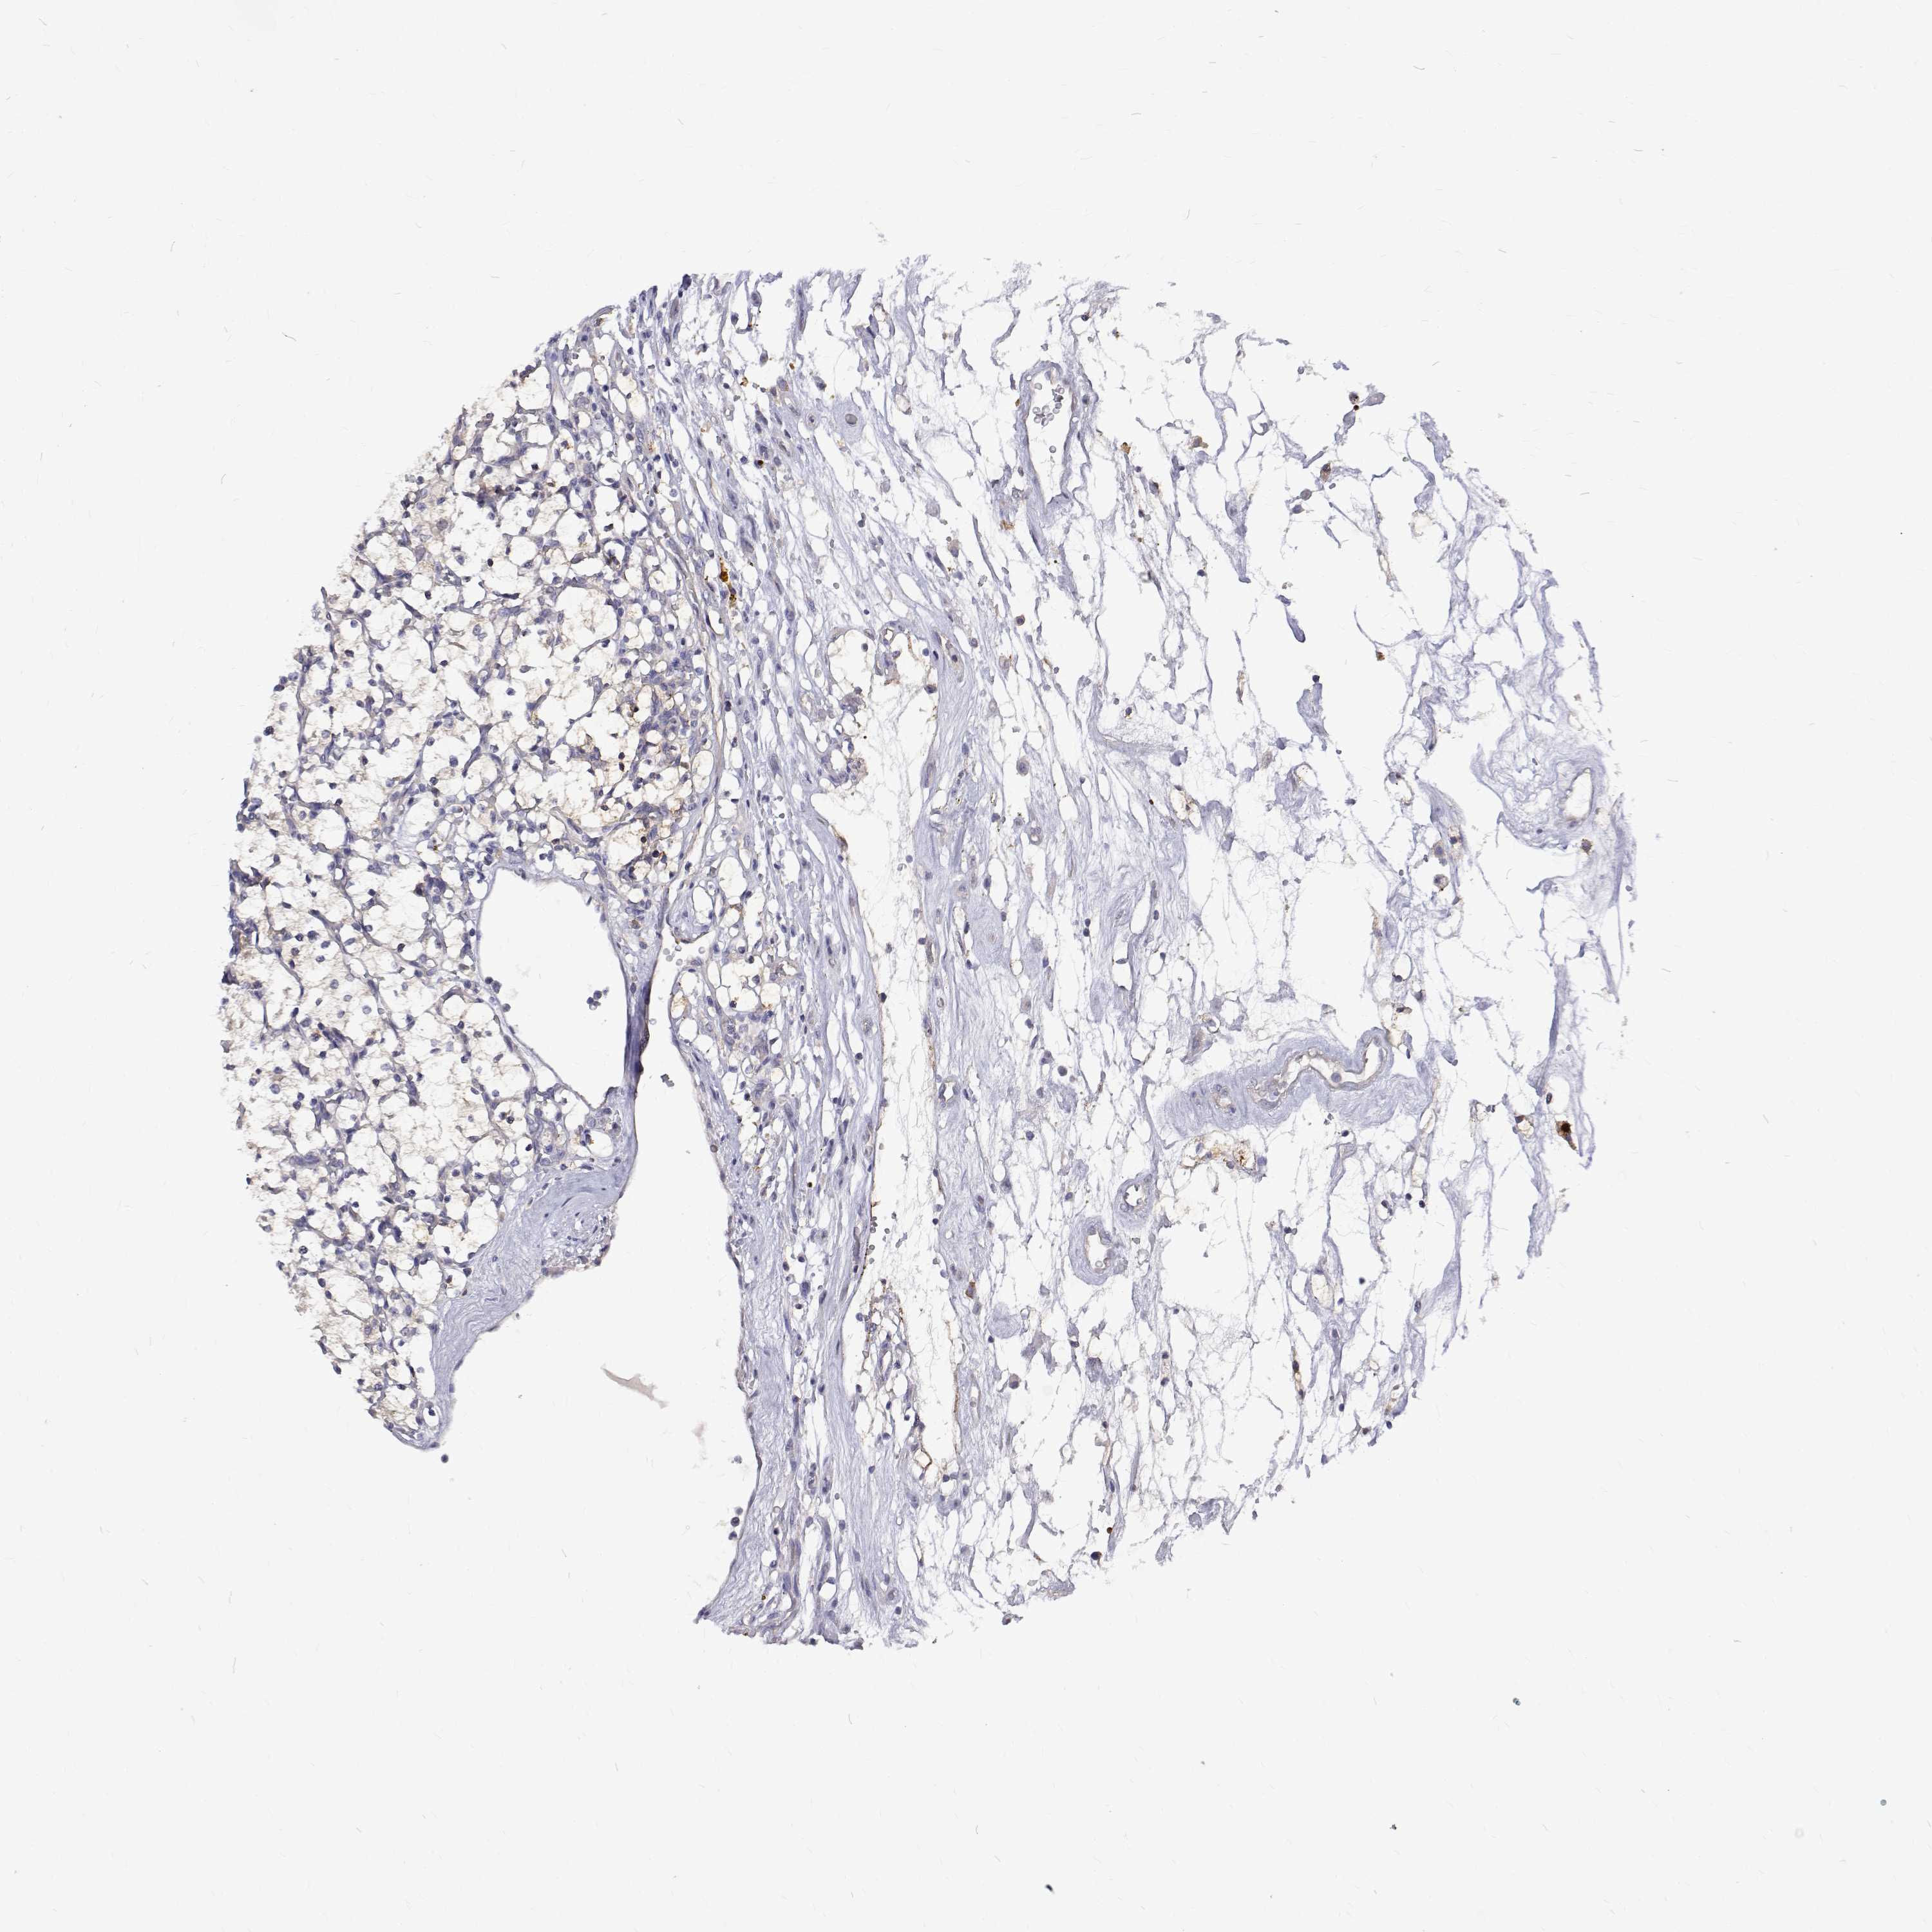

KIDNEY RENAL PAPILLARY CELL CARCINOMA (TCGA) - Interactive survival scatter ploti

The Survival Scatter plot shows the clinical status (i.e. dead or alive) for all individuals in the patient cohort, based on the same data that underlies the corresponding Kaplan-Meier plots. Patients that are alive at last time for follow-up are shown in blue and patients who have died during the study are shown in red.

The x-axis shows the expression levels (FPKM) of the investigated gene in the tumor tissue at the time of diagnosis. The y-axis shows the follow-up time after diagnosis (years). Both axes are complimented with kernel density curves demonstrating the data density over the axes. The top density plot shows the expression levels (FPKM) distribution among dead (red) and alive patients (blue). The right density plot shows the data density of the survived years of dead patients with high and low expression levels respectively, stratified using the cutoff indicated by the vertical dashed line through the Survival Scatter plot. This cutoff is automatically defined based on the FPKM cutoff that minimizes the p-score. The cutoff can be changed by dragging the vertical line or by entering a cutoff value in the square labeled "Current cut-off".

Under the Survival Scatter plot the p-score landscape (black curve; left axis) is shown together with dead median separation (red curve; right axis). Dead median separation is the difference in median mRNA expression between patients who have died with high and low expression, respectively. It is calculated as follows: median FPKM expression of dead patients with high expression - median FPKM expression of dead patients with low expression. This is intended to aid the user in visually exploring custom cutoffs and the associated p-scores and dead median separation.

Individual patient data is displayed and can be filtered by clicking on one or more of the category buttons on the top of the page. Categories describing expression level and patient information include: high, low, alive, dead, female, male and tumor stages. The scale of the x-axis can be toggled between linear and log-scale by clicking on the "x log" button. Mouse-over function shows TCGA ID, patient information and mRNA expression (FPKM) for each patient.

& Survival analysisi

Kaplan-Meier plots summarize results from analysis of correlation between mRNA expression level and patient survival. Patients were divided based on level of expression into one of the two groups "low" (under cut off) or "high" (over cut off). X-axis shows time for survival (years) and y-axis shows the probability of survival, where 1.0 corresponds to 100 percent.

PADI1 is not prognostic in Kidney Renal Papillary Cell Carcinoma (TCGA)

Best expression cut offi

Based on the FPKM value of each gene, patients were classified into two groups and association between prognosis (survival) and gene expression (FPKM) was examined. The best expression cut-off refers the FPKM value that yields maximal difference with regard to survival between the two groups at the lowest log-rank P-value. Best expression cut-off was selected based on survival analysis .

When clicking on this number, the vertical dashed line indicating cut-off, the interactive survival plot, and the Kaplan-Meier curve will be adjusted to show results based on the best expression cut-off.

: N/A

TCGA RNA samplesi

RNA-seq data is reported as average FPKM (number Fragments Per Kilobase of exon per Million reads), generated by the The Cancer Genome Atlas (TCGA) .

Normal distribution across the dataset is visualized with box plots, shown as median and 25th and 75th percentiles. Points are displayed as outliers if they are above or below 1.5 times the interquartile range. FPKM values of the individual samples are presented next to the box plot.

Average pTPM 0.2

Number of samples 282